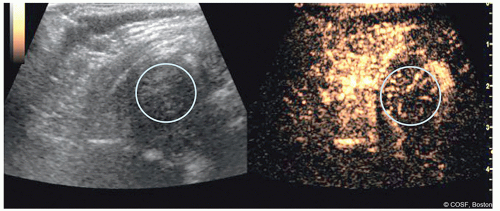

Proximal femoral perfusion can be assessed using intravenous contrast

Perfusion can be graded as “good,” “partial decrease,” or “global decrease” in perfusion

Assessment is performed before attempted reduction and after casting as part of the reduction assessment (Figures 20.6 and 20.7)

Figure 20-7 ▪ Contrast-enhanced ultrasound after attempted closed reduction and decreased perfusion. (Courtesy of Children’s Orthopaedic Surgery Foundation.)

Preliminary data points to a strong correlation between decreases in perfusion and eventual development of proximal femoral growth disturbance (PFGD)

Technique requires prior agreement with your radiology department and access to appropriate ultrasound machine and intravenous contrast agent